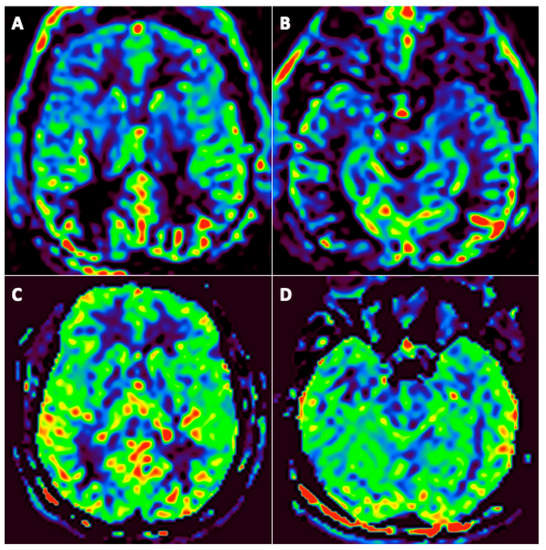

3.3. FDG-PET/CT Findings

- -

- One patient had PET in the acute phase;

- Twenty-three patients had PET at three months (among them, 12 underwent a second PET at six months);

- One patient underwent PET at six months.